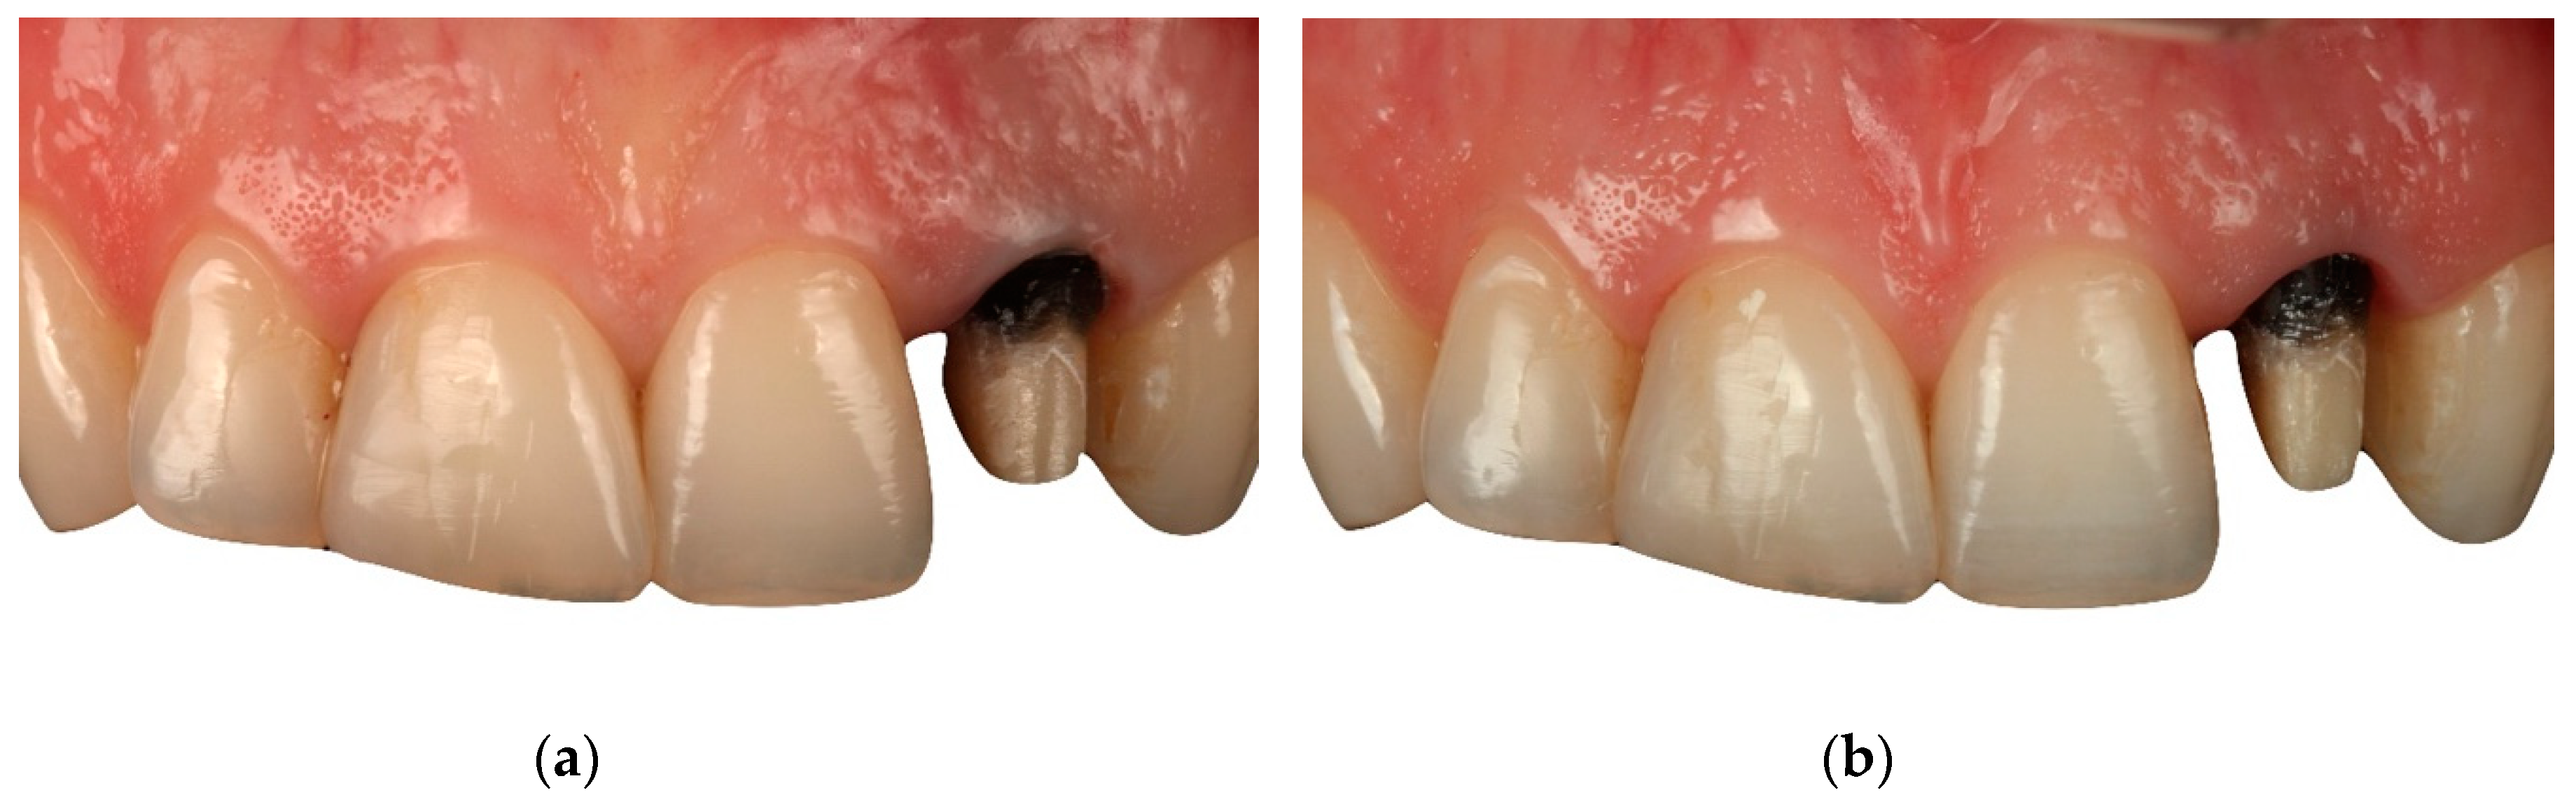

The clinical experience of BOPT reported in the literature has established that this technique increases the thickness of gingival tissue and enhances the stability of the soft tissue in the medium- and long-term compared to other classical preparations with finishing lines [5,7,8] (Figure 16, Figure 17, Figure 18, Figure 19 and Figure 20).

Figure 16. Retreatment of a fixed prosthesis with the BOPT technique. Initial pretreatment situation (Front view).

Applsci 10 04108 g016

Figure 17. Retreatment of a fixed prosthesis with the BOPT technique. Initial pretreatment situation (Lateral view).

Applsci 10 04108 g017

Figure 18. Gingiva after perioperative treatment with BOPT.

Applsci 10 04108 g018

Figure 19. Situation after treatment with BOPT (Front view).

Applsci 10 04108 g019

Figure 20. Situation after treatment with BOPT (Lateral view).